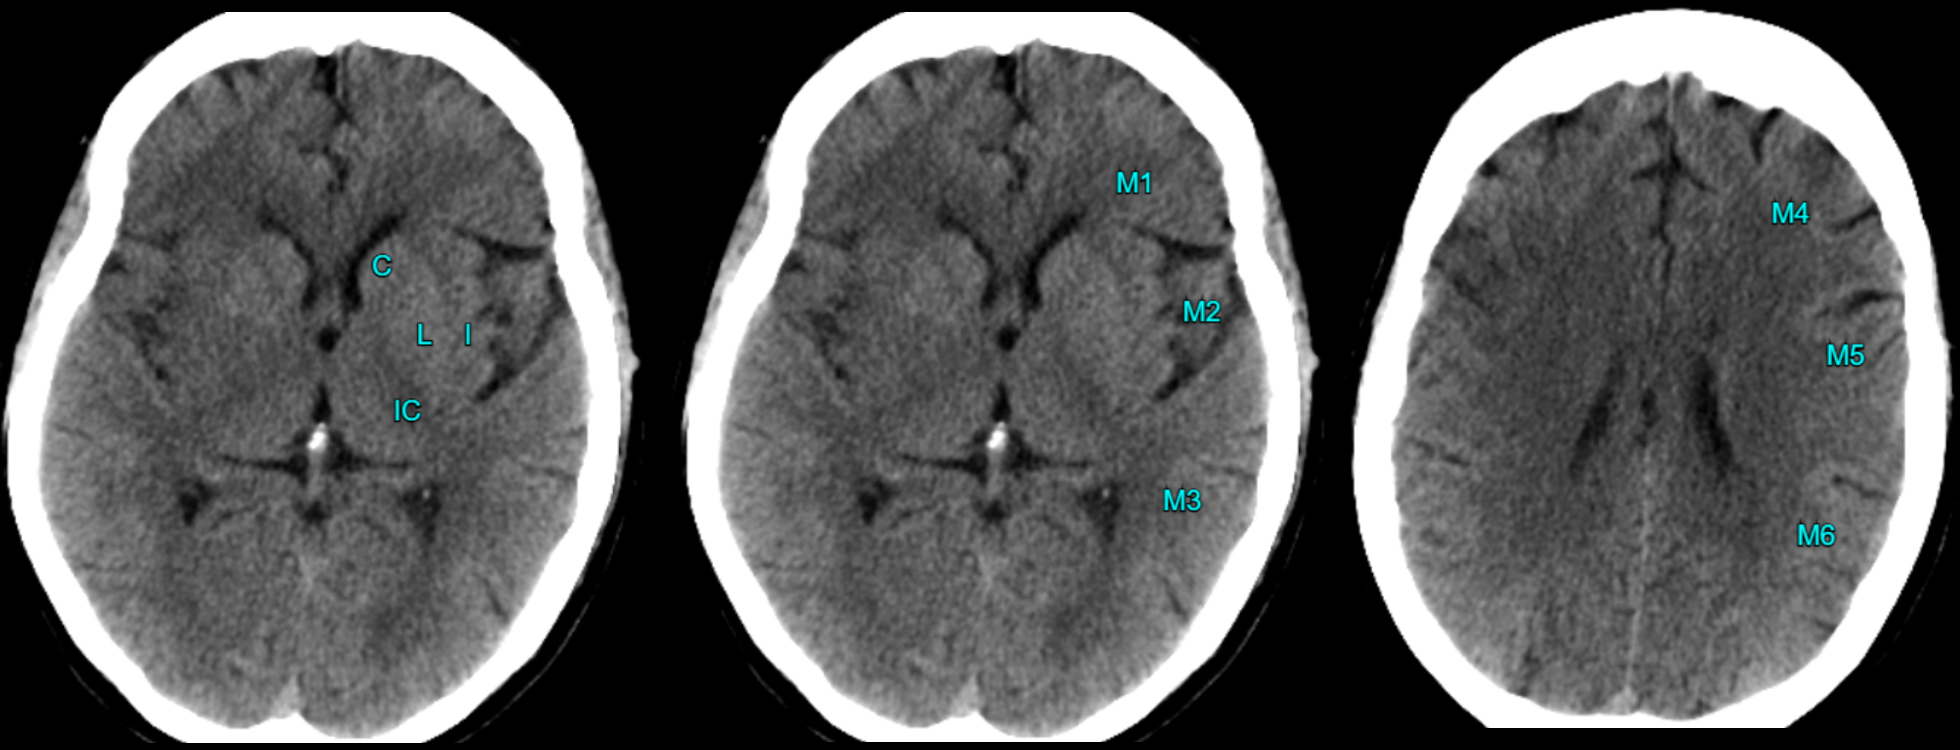

Điểm CTscan sớm của Chương trình Đột quỵ Alberta (ASPECTS) giúp đánh giá vùng tổn thương do tắc/ hẹp cấp tính chủ yếu thuộc vùng cấp máu của động mạch não giữa (MCA).

CTscan (không tiêm thuốc cản quang) trong giai đoạn sớm dựa trên 2 lát cắt chính:

- Lát cắt đi ngang vùng đồi thị - hạch nền và

- Lát cắt phía trên hạch nền (không thấy hạch nền).

- Mất sự khác biệt giữa chất trắng và chất xám trong vùng hạch nền (ví dụ: che lấp nhân đậu[nhân bèo]).

- Mất dải Thùy đảo hoặc che lấp khe Sylvian.

- Giảm tỷ trọng vùng vỏ não và xóa rãnh cuộn.